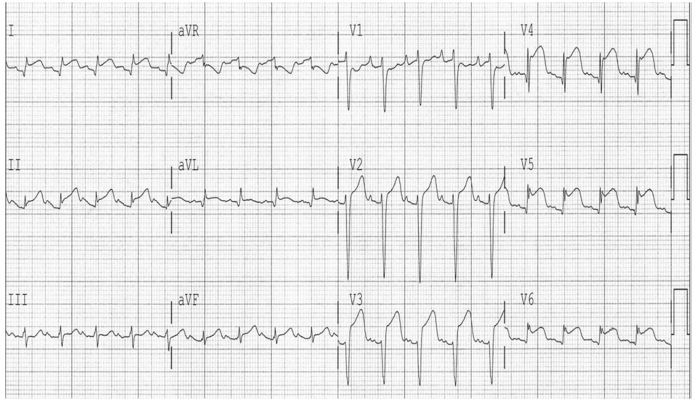

Mulher de 60 anos com HAS e DM tipo 2, relata dor torácica retroesternal em aperto de início há 90 minutos, associada à dispneia, que

começou logo após ser informada do falecimento de seu irmão.

Ao exame: taquidispneica em ar ambiente, sudoreica, corada, acianótica. FC: 120 bpm; PA: 118x64 mmHg. MVUA com crepitação nos 1/3

inferiores bilateralmente. Ritmo cardíaca regular em 3 tempos (B3), bulhas normofonéticas, sem sopros ou turgência jugular patológica a

90º

. O restante do exame físico foi normal.

O eletrocardiograma de admissão encontra-se abaixo e a primeira aferição de troponina ultrassensível foi positiva.

Assinale a opção que apresenta o diagnóstico mais provável.